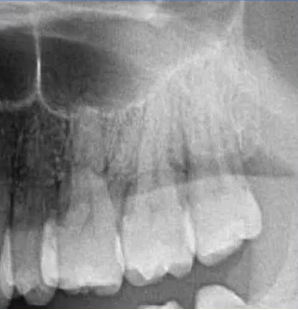

查:14残根,牙龈红肿;35叩诊(+),45叩诊(+),牙颌面见畸形中央尖。

35叩诊(+)

二次拍根尖片确认可看到根尖低密度炎症,临床检查与影像学检查相符,是根尖周炎。

曲面断层片怎么看口腔精读 | 一次性教你看懂曲面断层片!_https://www.jmylbn.com_新闻资讯_第21张

临床检查时发现14残根,牙龈红肿。曲面断层片上由于前磨牙转角问题,看不到残根,无法明确到底有没有残根,无法通过曲面断层片进行确诊或评估。

曲面断层片怎么看口腔精读 | 一次性教你看懂曲面断层片!_https://www.jmylbn.com_新闻资讯_第22张

这时需要加拍根尖片,很明显能看到残根。这就说明,有曲面断层片也不能排除情况。

临床检查45叩诊(+),牙颌面见畸形中央尖。加拍根尖片可看到,右下5根方有低密度影,并且右下5的牙根较短小,和曲面断层片上显示的大小不同,所以右下5是舌向倾斜的牙齿。